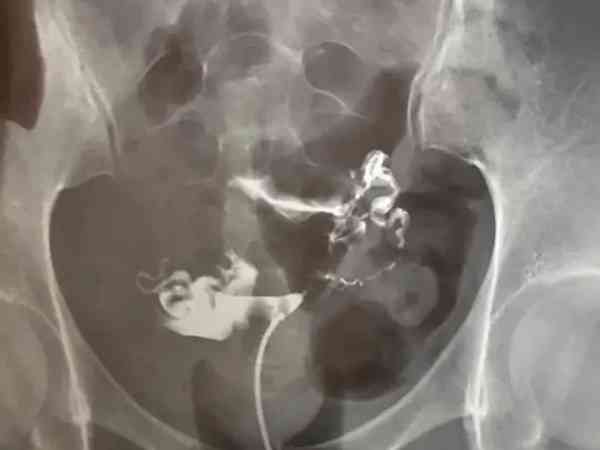

网上1分钟教你看输卵管造影片子主要是通过造影显影图来进行输卵管情况判定的,从图片上可以很直观的看出输卵管通畅、输卵管梗阻、输卵管积水三种情况,其中输卵管梗阻(堵塞)和输卵管积水对于自然备孕是有一定影响的,怀孕几率会有所降低,三种情况具体的判定方法可以参考以下:1、输卵管通畅输卵管通畅在造影片子上可以看到一侧或双侧输卵管伞端有造影剂溢出,盆腔中也会出现造影剂涂抹,之后积极试孕,在排除其他影响不孕不育...